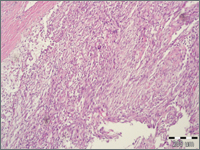

Internal MedicineFibroblastoma desmoplasticum (collagenous fibroma) is a rare benign soft tissue tumor. So far about 120 cases have been described in the literature. The most common location is the subcutaneous tissue of the extremities and neck. It occurs most often in men, in the fifth and sixth decades of life. It is usually well-demarcated, elastic, slow-growing, non-painful tumor. The treatment of choice is simple surgical removal. Recurrences have not been observed.